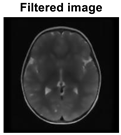

A growth that may adversely impact a person’s life is a brain tumor, which can appear in the tissues enclosing the brain or skull. Two characteristics can identify a benign or malignant growth. While secondary tumors, also referred to as brain metastasis tumors, are typically formed from tumors outside the brain, primary cancers start inside the brain. Meningiomas, pituitary adenomas, and gliomas are the three most common primary brain tumors. The brain and spinal cord membrane layers are the origin of meningiomas, a type of tumor that grows slowly. Cancerous cells that arise in the pituitary gland are referred to as pituitary adenomas [1]. The brain tissue is compressed by the irregular growth of these tumors. Malignant tumors, in comparison with benign tumors, grow unevenly and damage the tissues around them. Surgical techniques are frequently employed in the treatment of brain tumors [2]. Because MRI is non-interfering, it is preferred over computed tomography (CT), positron emission tomography (PMT), and x-rays [3]. It is estimated that 79,340 Americans aged 40 and older will be diagnosed with a primary brain tumor by 2023. It is estimated that one million Americans suffer from primary brain tumors; of these, 72% are benign tumors and 28% are malignant. The adults with primary brain tumors typically have meningioma (46.1%), glioblastoma (16.4%), and pituitary tumors (14.5%) [4,5]. Biopsies are taken for analysis after the tumor is found using standard medical techniques like MRI. The first test used in medicine to find cancer is MRI [6,7]. Two MRI pictures of two distinct brains are shown in Figure 1.

Figure 1. MRI scans performed on two different brains. (a) On the left is a tumor, and (b) on the right is a healthy brain [8].